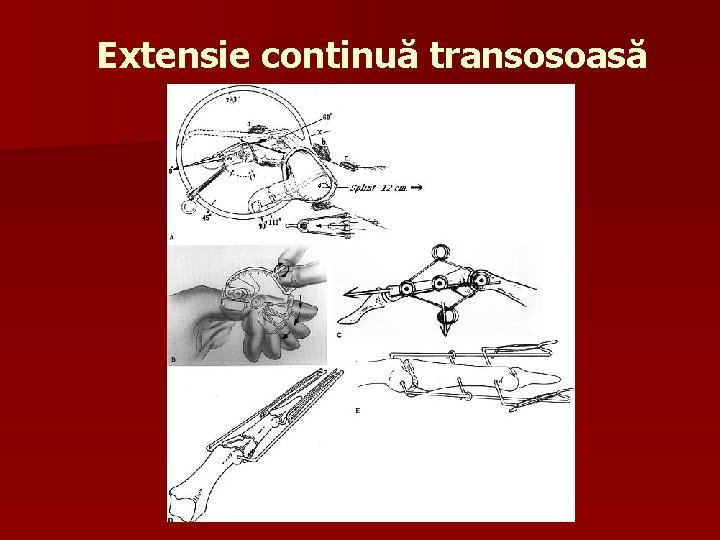

Extensie continuă transosoasă